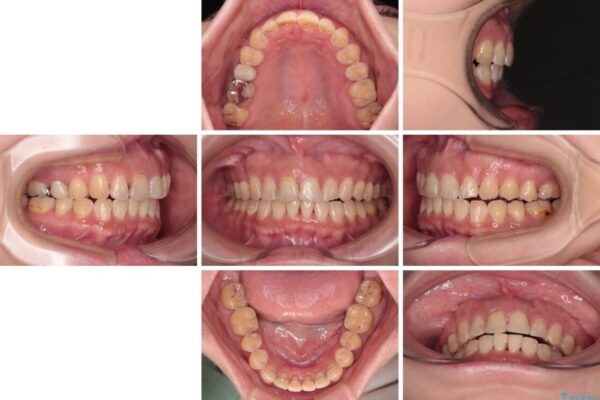

治療後について

舌の突出癖が原因で上下の歯に大きなスペースが生じていたため、舌のトレーニングをしっかり行っていただくことで、上顎歯列をスムーズに移動させることができました。

治療後

• 【モニター】飛び出た前歯を整えたい ワイヤー矯正治療 治療後画像